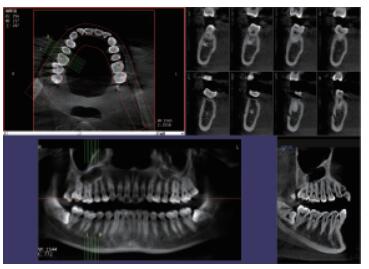

4、口腔CBCT(口腔CT)

CT相對其他牙片來講,不管是功能還是設(shè)備上都是比較高級的,醫(yī)生可在電腦上進行模擬種植360°的旋轉(zhuǎn)查看口腔狀況,不遺漏任何一個角落,主要用于根管治療前、阻生牙、根尖囊腫、種植牙、正畸等。